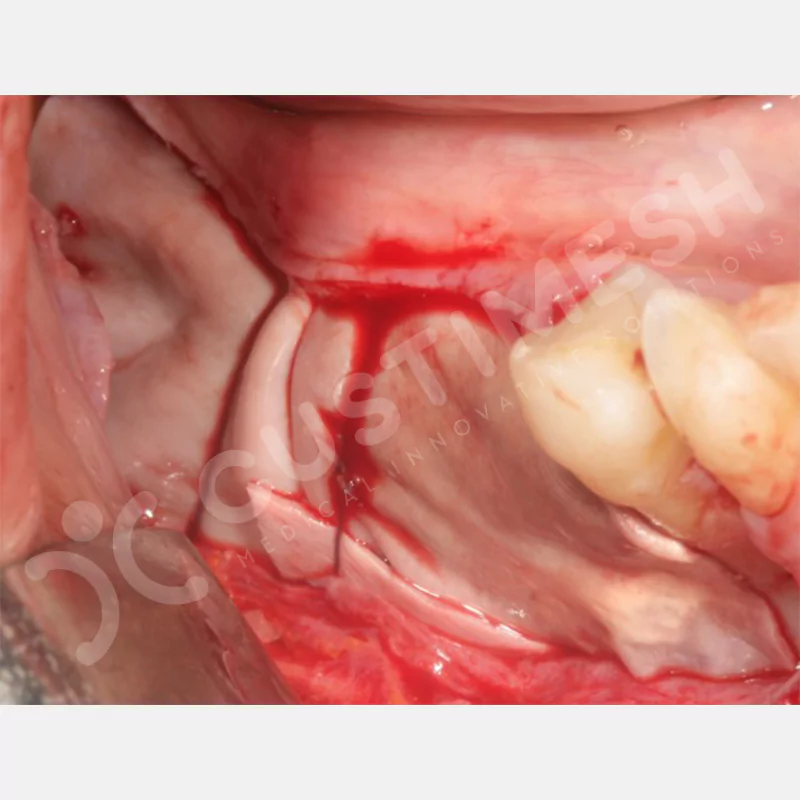

VAKA 1